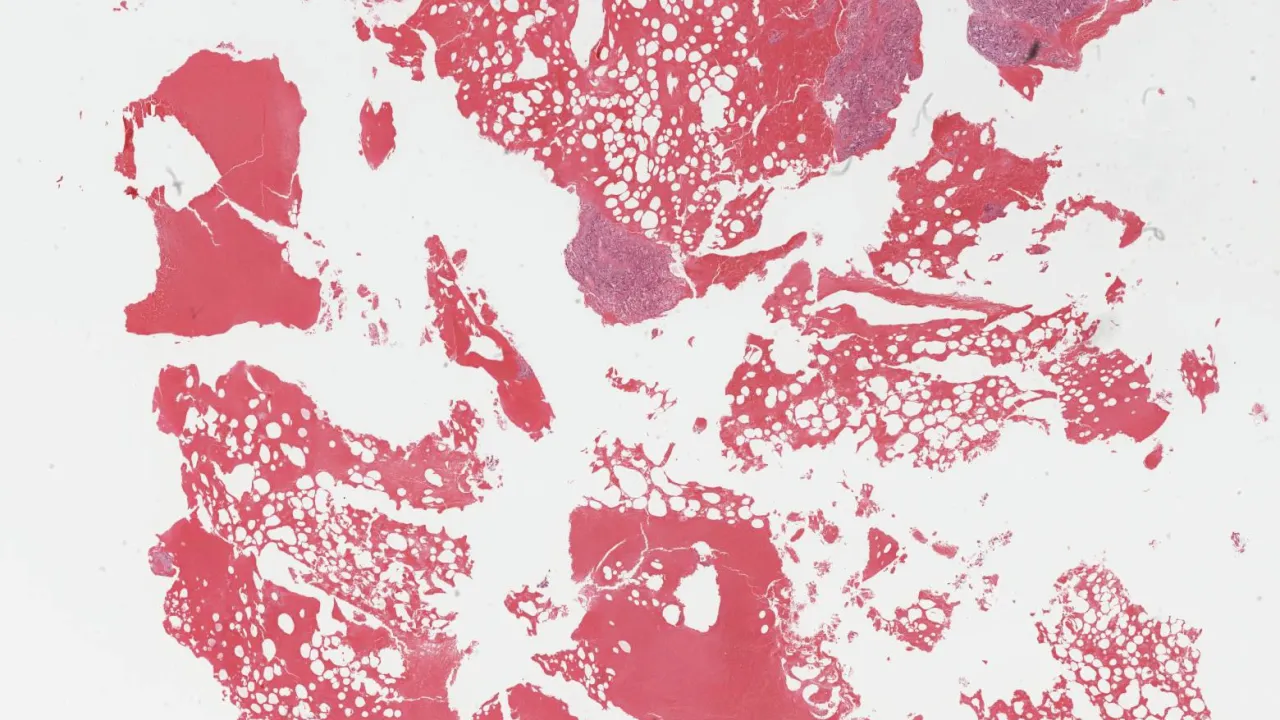

Soft Tissue, Extramedullary hematopoiesis